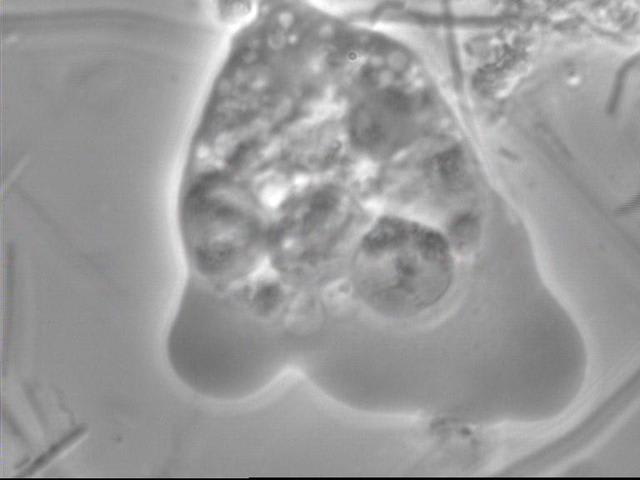

un trichomonas.

Attends d'avoir vu des trichomonas! Il n'y a pas les yeux, mais les tentacules et les petites jambes sont là et après 3 mois chaque fois que j'en trouve, mon assistante fait un bond en arrière et une grimace!

Le 100x (c'est à dire 10x oculaire et 10x objectif) est très pratique pour balayer la totalité de la lame et éventuellement détecter les trichomonas (les plus faciles) à faible grossissement et ensuite scotcher le patient en tombant soi disant fortuitement dessus;-)

Je me rappelle du trichomonas, on dirait un blob avec une tête chercheuse, peu ragoutant.

Encore quelques photos:

Une amibe qui boulote un globule bien vivant. A noter que le globule en haut du cliché était bien circulaire et vivant (les petits "granulés" bougent dans tous les sens) 1 minute avant l'agression